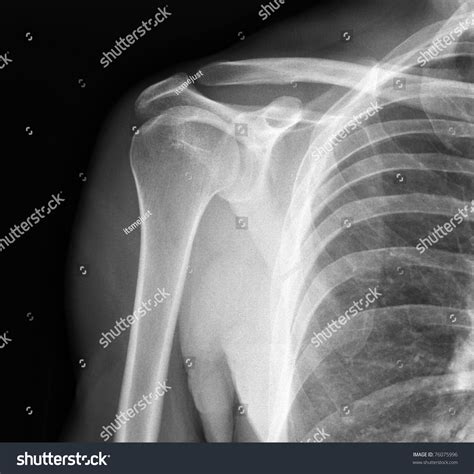

Advanced Imaging Techniques

While X Ray Shoulder Joint imaging is a valuable diagnostic tool, there are times when more detailed information is needed. In such cases, advanced imaging techniques may be employed:

• MRI (Magnetic Resonance Imaging): Provides detailed images of soft tissues, including muscles, tendons, and ligaments.

• CT (Computed Tomography) Scan: Offers cross-sectional images of the shoulder, useful for detecting complex fractures and bone abnormalities.

• Ultrasound: Uses sound waves to visualize soft tissues and can be particularly useful for diagnosing rotator cuff tears.

These advanced techniques complement X Ray Shoulder Joint imaging by providing a more comprehensive view of the shoulder joint.